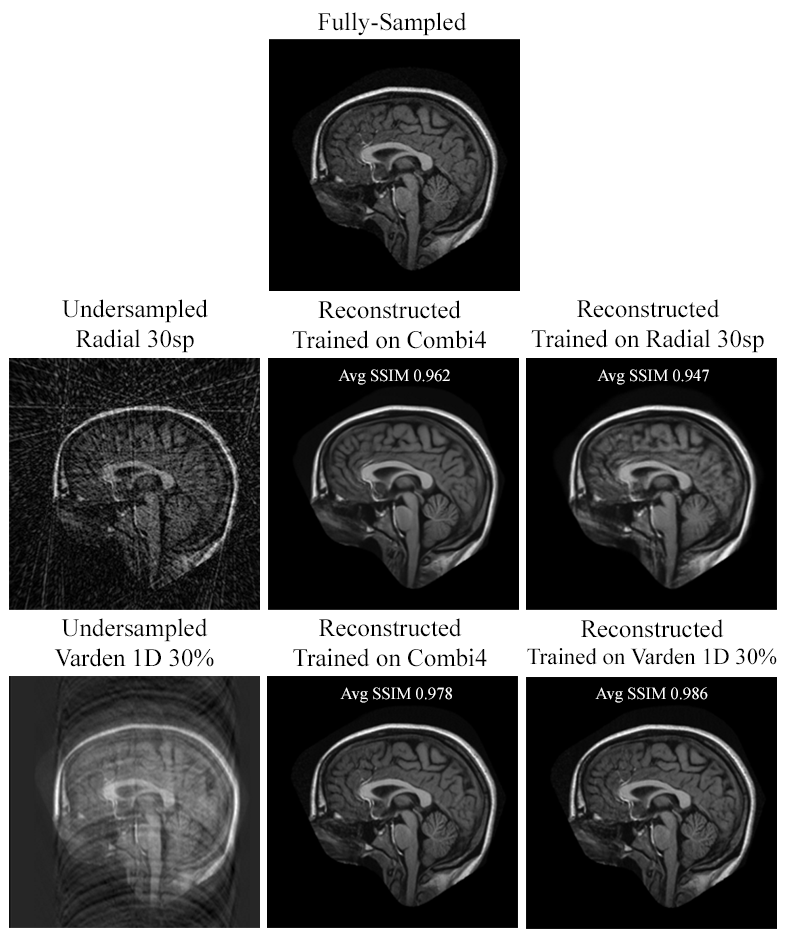

As illustrated in Fig. 20, the Combi4 model can be taken as an efficient general model to reconstruct any under-sampling pattern. In the case of reconstructed Radial under-samplings, the Combi4 model was better than the individually trained models of the corresponding under-sampling patterns. In particular, Combi4 had a slightly lower variance than the specific model in reconstructing Radial 60 spokes. Additionally, the mean of the Combi4 model was higher and the variance was better in comparison to the specific model in reconstructing Radial 30 spokes. On the other hand, the plot shows that using a Combi2 model on the same volume yields the same mean but a slightly better variance reconstructing Radial 60 spokes than the specific model. Combi2 models also have the same variance and mean reconstructing Varden 1D 30% in comparison to its specific model. Fig 18 shows an example reconstruction of Radial 30sp and 1D Varden 30%, where it can be seen that Combi4 is better by 0.015 in reconstructing Radial 30 and, specific Varden 1D 30% trained model does 0.008 better in estimating the fully-sampled than Combi4 (while comparing the average SSIM values). However, Combi4 model did better on Varden 1D patterns with less than 30% under-sampling than the Varden 1D 30p trained model (see Fig. 20).

Refer to caption

Figure 18: Example reconstructions of Radial 30sp and 1D Varden 30% data: comparing reconstruction quality while being trained on a specific sampling pattern (the one used for reconstruction) or trained on four patterns together (Combi4). Average SSIM values obtained for that specific setup on the whole OASIS dataset are also shown here.